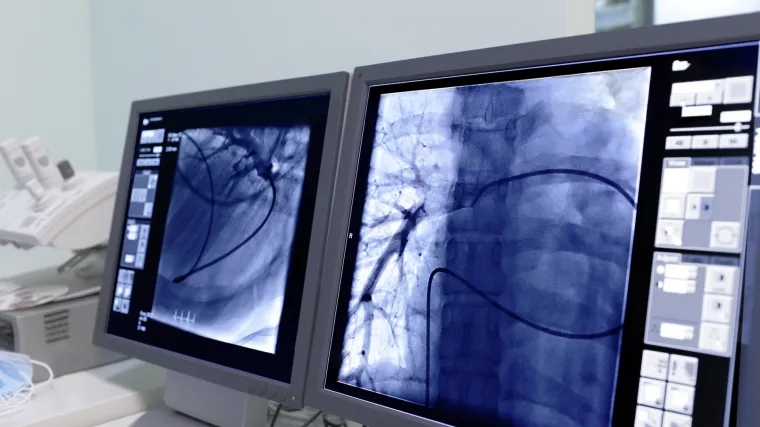

Analiza CT-snimaka može biti rano upozorenje na opasnost od srčanog udara?

Novom metodom analize snimaka moguće je predvidjeti kojim pacijentima prijeti srčani udar i to godinama prije nego se dogodi

Tehnologiju su znanstvenici s Oxforda razvili u suradnji s ustanovama u Njemačkoj i Sjedinjenim Državama koristeći se algoritmovima kako bi proučili masnoće nakupljene oko koronarnih arterija prikazanih na snimkama srca učinjenih CT-om.

Masnoće se mijenjaju kada se arterija upali i to može služiti kao sustav ranog upozorenja u 30 posto slučajeva srčanih udara, kažu znanstvenici. "Ako možete identificirati upalu arterija srca tada možete reći koja arterija... će izazvati srčani napad", kaže oxfordski profesor Charalambos Antoniades. S novom tehnologijom to je moguće ako se analiziraju CT-snimke.

Srčani i moždani udari dva su najveća uzročnika smrti u svijetu

Većinu srčanih udara izaziva nakupljanje masnoća na unutrašnjoj stjenci arterija što sužava žilu, smanjuje njezinu prohodnost i dotok krvi u srce. Za sada snimke CT-a pokazuju liječnicima mjesto na kojem je arterija već sužena zbog nakupljanja masnoća, no s novom tehnologijom liječnici će moći predvidjeti kojim arterijama prijeti suženje.  Znanstvenici se nadaju da će je odobriti nadležne vlasti s obje strane Atlantika u roku od godine dana.

"Možemo reći...  vaše su arterije upaljene i suženje će se dogoditi u roku od pet godina. Stoga možda možete već danas početi poduzimati preventivne mjere kako biste spriječili formiranje naslaga masnoća,  kaže Antoniades.

Srčani i moždani udari dva su najveća uzročnika smrti u svijetu.  "Iako nismo procijenili točan broj srčanih udara koje je moguće spriječiti, potencijalno možemo identificirati najmanje 20 ili 30 posto ljudi kojima udar prijeti", zaključuje  Antoniades.

Tvrtka u suradnji s Oxfordom već je počela razvijati službu koja bi analizirala CT u roku od 24 sata diljem svijeta.  Istraživanje je objavljeno u medicinskom časopisu  The Lancet